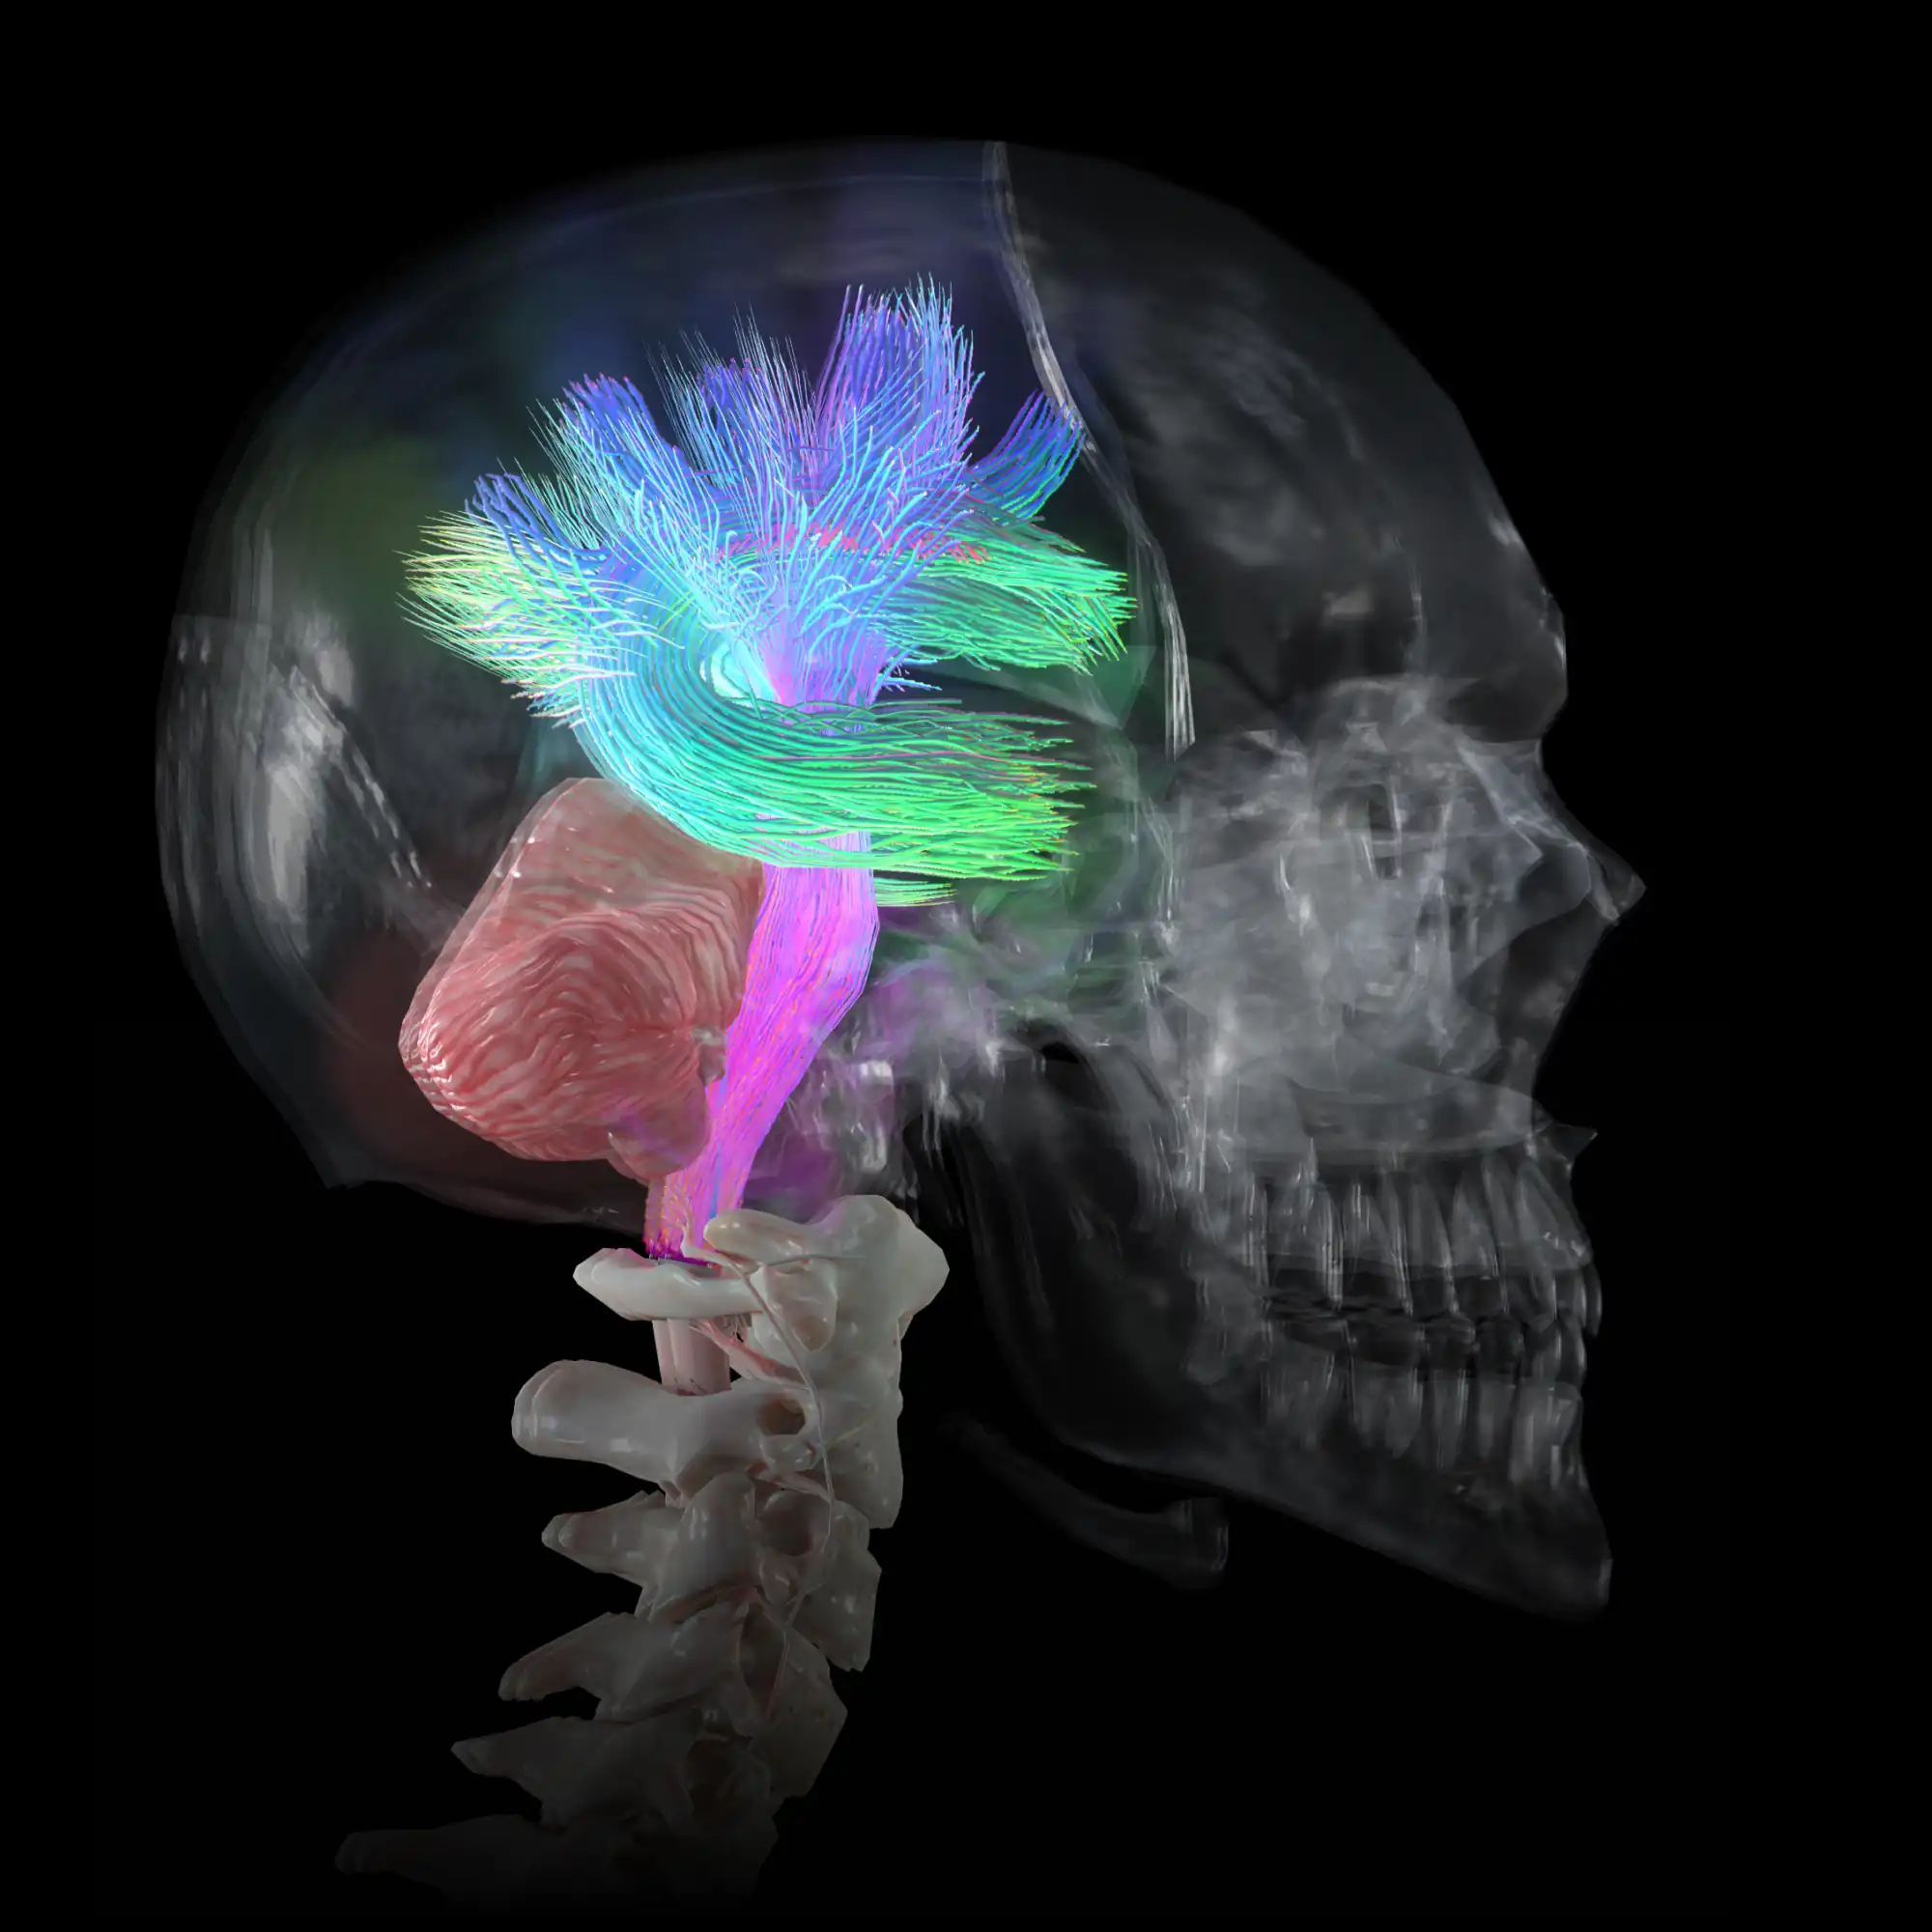

High definition models.

You will get 5,000 meticulously detailed anatomy models, designed to meet rigorous industry standards. Our in-house team has carefully crafted each 3D element, ensuring that you have access to the most accurate and highest quality models available on the market.

High definition models.

You will get 5,000 meticulously detailed anatomy models, designed to meet rigorous industry standards. Our in-house team has carefully crafted each 3D element, ensuring that you have access to the most accurate and highest quality models available on the market.

Full-body 3D learning.

Whether focusing in on the cardiovascular system, skeletal framework, nervous system or more, our immersive 3D experience brings the entire body to life. Perfect for learners at any level.